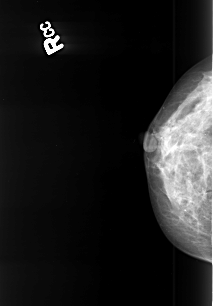

B_3418_1.RIGHT_CC

RIGHT_CC LINES 3976 PIXELS_PER_LINE 2768 BITS_PER_PIXEL 12 RESOLUTION 50 NON_OVERLAY